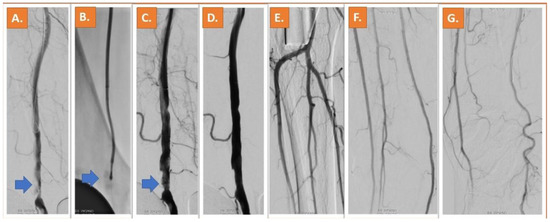

Representative Cases: Two cases of patients who underwent Jetstream and Phoenix atherectomy are shown in Figure 1 and Figure 2.

Figure 1. A chronic moderately calcified occlusion of the popliteal artery can be depicted in (A). Treatment was successfully performed with Jetstream rotational atherectomy after placement of a filter system (B). The result after Jetstream-assisted atherectomy and DCB can be appreciated in (C) [11].